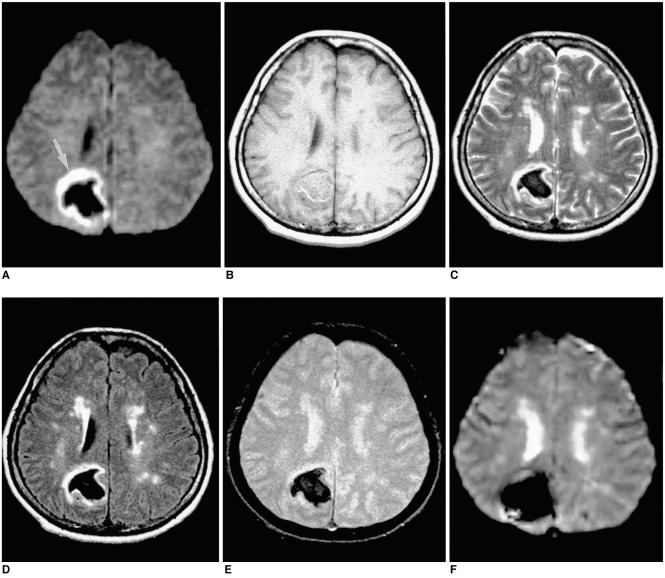

To document the signal characteristics of intracerebral hemorrhage (ICH) at evolving stages on diffusion-weighted images (DWI) by comparison with conventional MR images.

In our retrospective study, 38 patients with ICH underwent a set of imaging sequences that included DWI, T1-and T2-weighted imaging, and fluid-attenuated inversion recovery (FLAIR). In 33 and 10 patients, respectively, conventional and echo-planar T2* gradient-echo images were also obtained. According to the time interval between symptom onset and initial MRI, five stages were categorized: hyperacute (n=6); acute (n=7); early subacute (n=7); late subacute (n=10); and chronic (n=8). We investigated the signal intensity and apparent diffusion coefficient (ADC) of ICH and compared the signal intensities of hematomas at DWI and on conventional MR images.

DWI showed that hematomas were hyperintense at the hyperacute and late subacute stages, and hypointense at the acute, early subacute and chronic stages. Invariably, focal hypointensity was observed within a hyperacute hematoma. At the hyperacute, acute and early subacute stages, hyperintense rims that corresponded with edema surrounding the hematoma were present. The mean ADC ratio was 0.73 at the hyperacute stage, 0.72 at the acute stage, 0.70 at the early subacute stage, 0.72 at the late subacute stage, and 2.56 at the chronic stage.

DWI showed that the signal intensity of an ICH may be related to both its ADC value and the magnetic susceptibility effect. In patients with acute stroke, an understanding of the characteristic features of ICH seen at DWI can be helpful in both the characterization of intracranial hemorrhagic lesions and the differentiation of hemorrhage from ischemia.